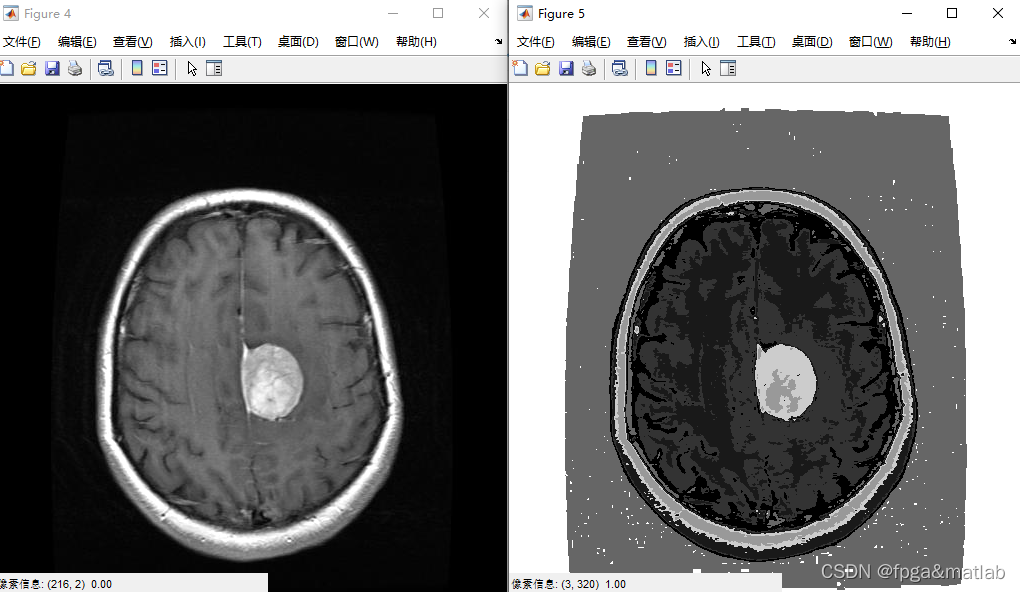

figure;imshow(I,[]);impixelinfo; % Show Image I

[center,U,obj_fcn] = fcm(data,7); % Fuzzy C-means classification with 7 classes

figure;imshow(imagNew,[]);impixelinfo;

该博客介绍了如何利用Matlab进行Fuzzy C-means(FCM)聚类,将两种不同的医学图像(GADO和AXIAL FLAIR)作为输入进行图像分割。通过调整像素值,将像素分配到7个不同的类别中,最终生成一个新的融合图像。这个过程对于医学影像分析和图像处理研究具有重要意义。